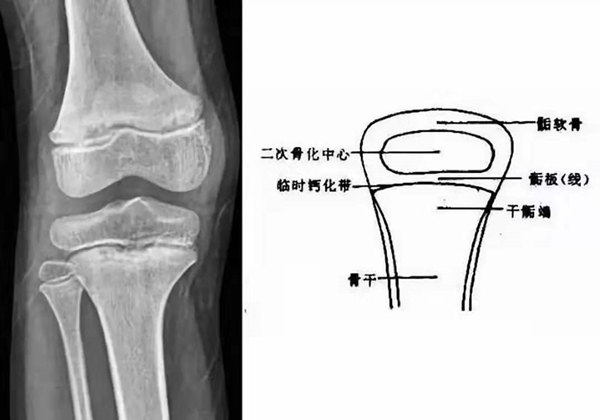

我們都知道,人體的高矮是由骨骼的生長發育決定的,特別是下肢長骨。長骨呈長管狀,在長骨的兩端有一種專管骨骼生長的骺軟骨,它與干骺端之間有一盤狀軟骨結構稱為骺板(線),在幼兒的X光片上表現為一條較寬的透光帶。 (見下圖)

未成年時隨著年齡的增加骺軟骨端不斷骨化,骨骼就不斷增長。當骨骺線完全閉合時骨骼就停止生長,個子也就不再增長了。一般骨骺端完全閉合的年齡是18~20歲左右。